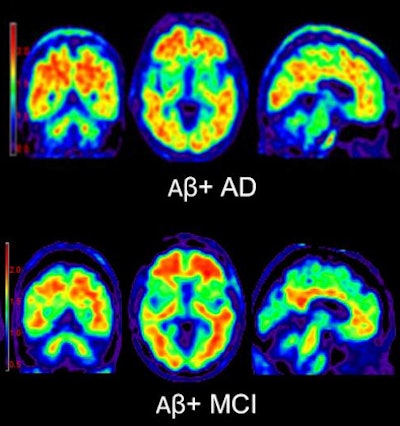

| PET images using florbetapir to highlight beta-amyloid plaque show, above, a cognitively normal subject and an amyloid-negative patient with MCI. Below is an amyloid-positive patient with Alzheimer's disease, as well as an amyloid-positive patient with MCI. All images courtesy of Neurology. |